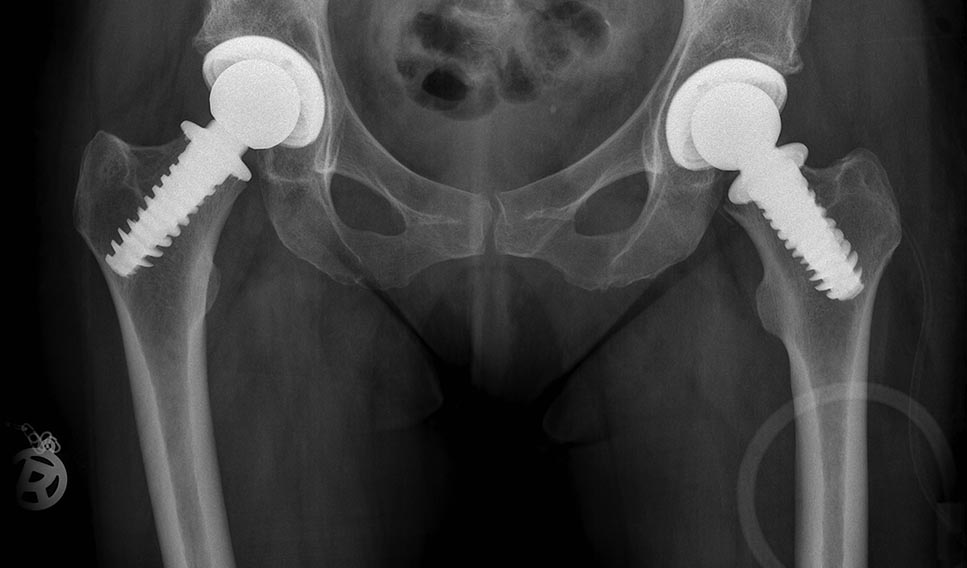

1.Spiron Prothes Firma K-Implant s prothesirowaniem wpadini kak na snimke!

2.Wtoroi wariant Dupkopf (Bipoljar) na korotkoi noschke (Brexis ili Nanos) no objasatel'no KERAMIKA s ispol'sowaniem sobstwennoj wpadini, no eto moschno delat' tol'ko esli hrjasch' sochranön!!!